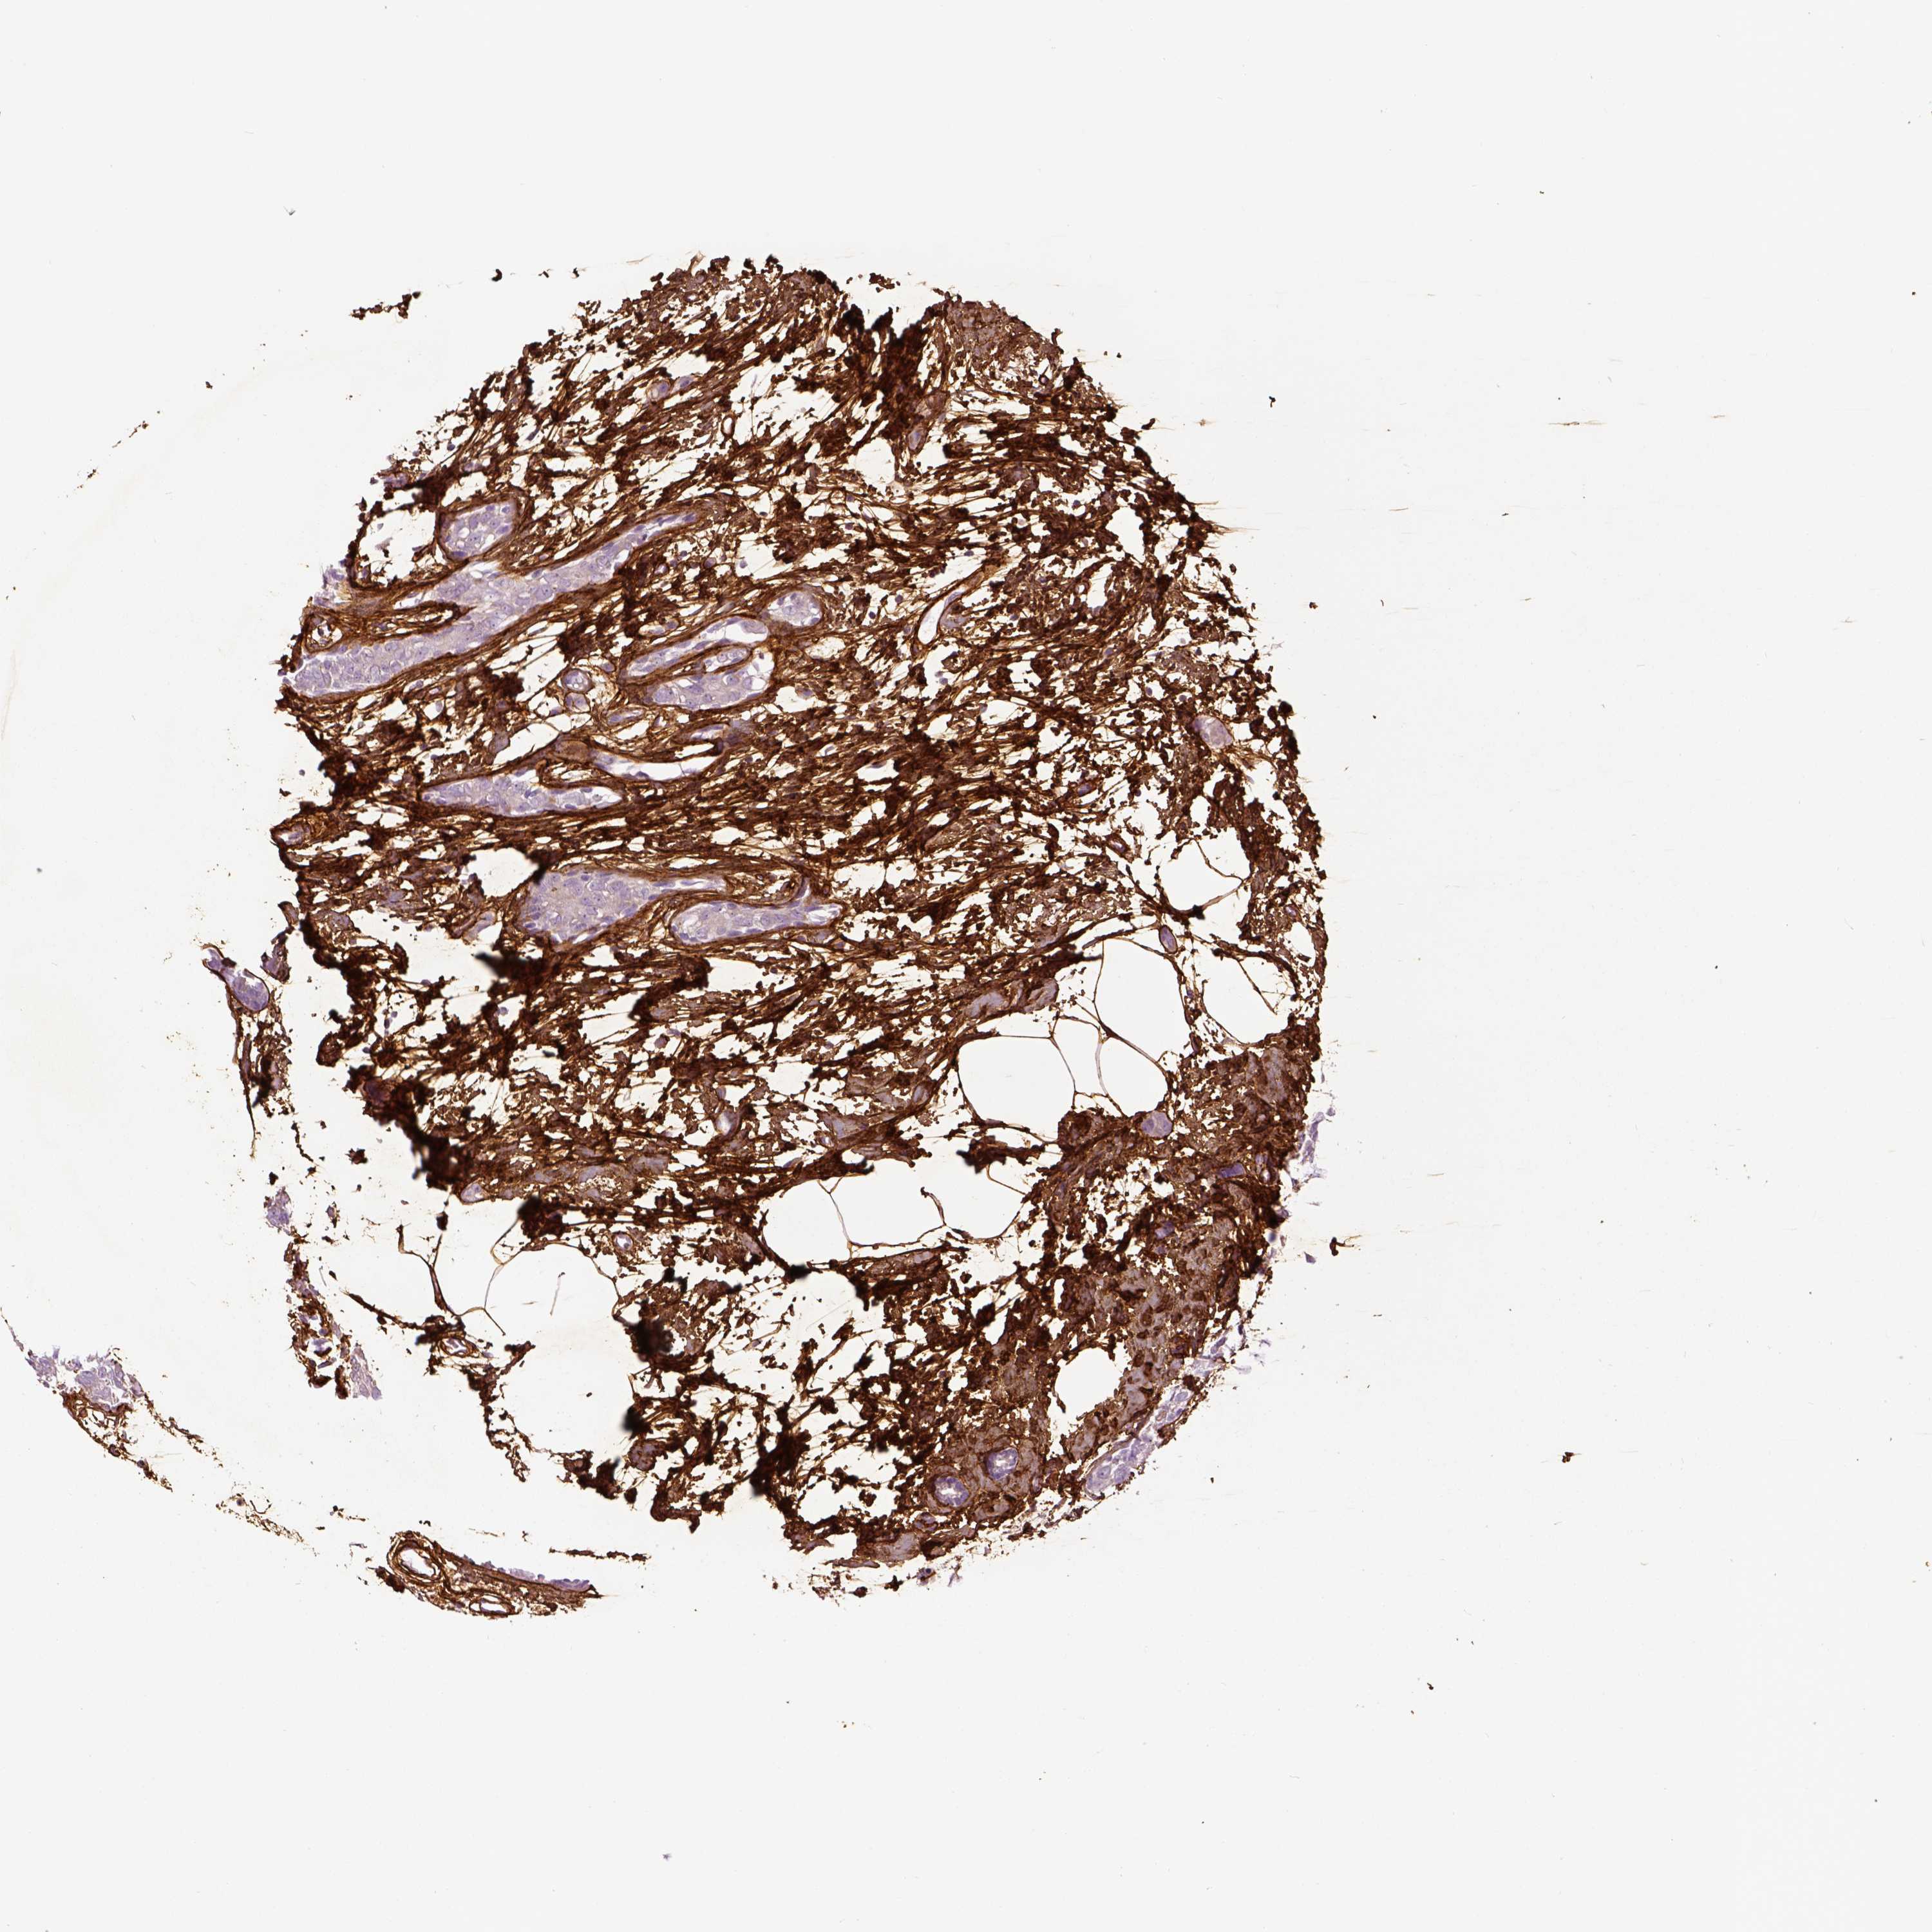

BRCA TCGA BRCA VALIDATION PROTEIN EXPRESSION